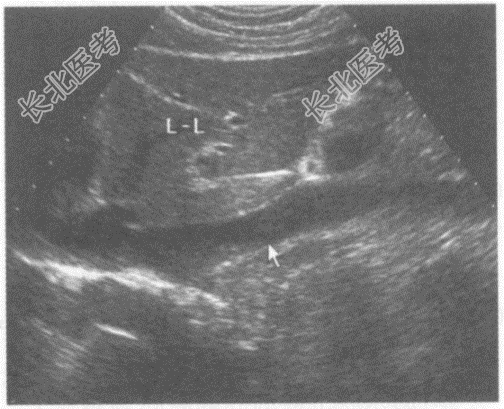

- 单项选择题请问下图是采用哪种肝脏扫查方式:

A、肝一腹主动脉纵切声像图

B、肝一胆囊纵切声像图

C、肝一下腔静脉纵切声像图

D、肝一胃纵切声像图

E、肝一脾静脉纵切声像图